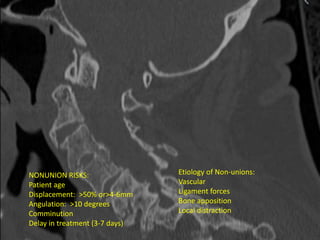

NONUNION RISKS:

Patient age

Displacement: >50% or>4-6mm

Angulation: >10 degrees

Comminution

Delay in treatment (3-7 days)

Etiology of Non-unions:

Vascular

Ligament forces

Bone apposition

Local distraction

NONUNION RISKS: Patient age Displacement:>50% or>4-6mm Angulation: >10 degrees Comminution Delay in treatment (3-7 days) Etiology of Non-unions: Vascular Ligament forces Bone apposition Local distraction